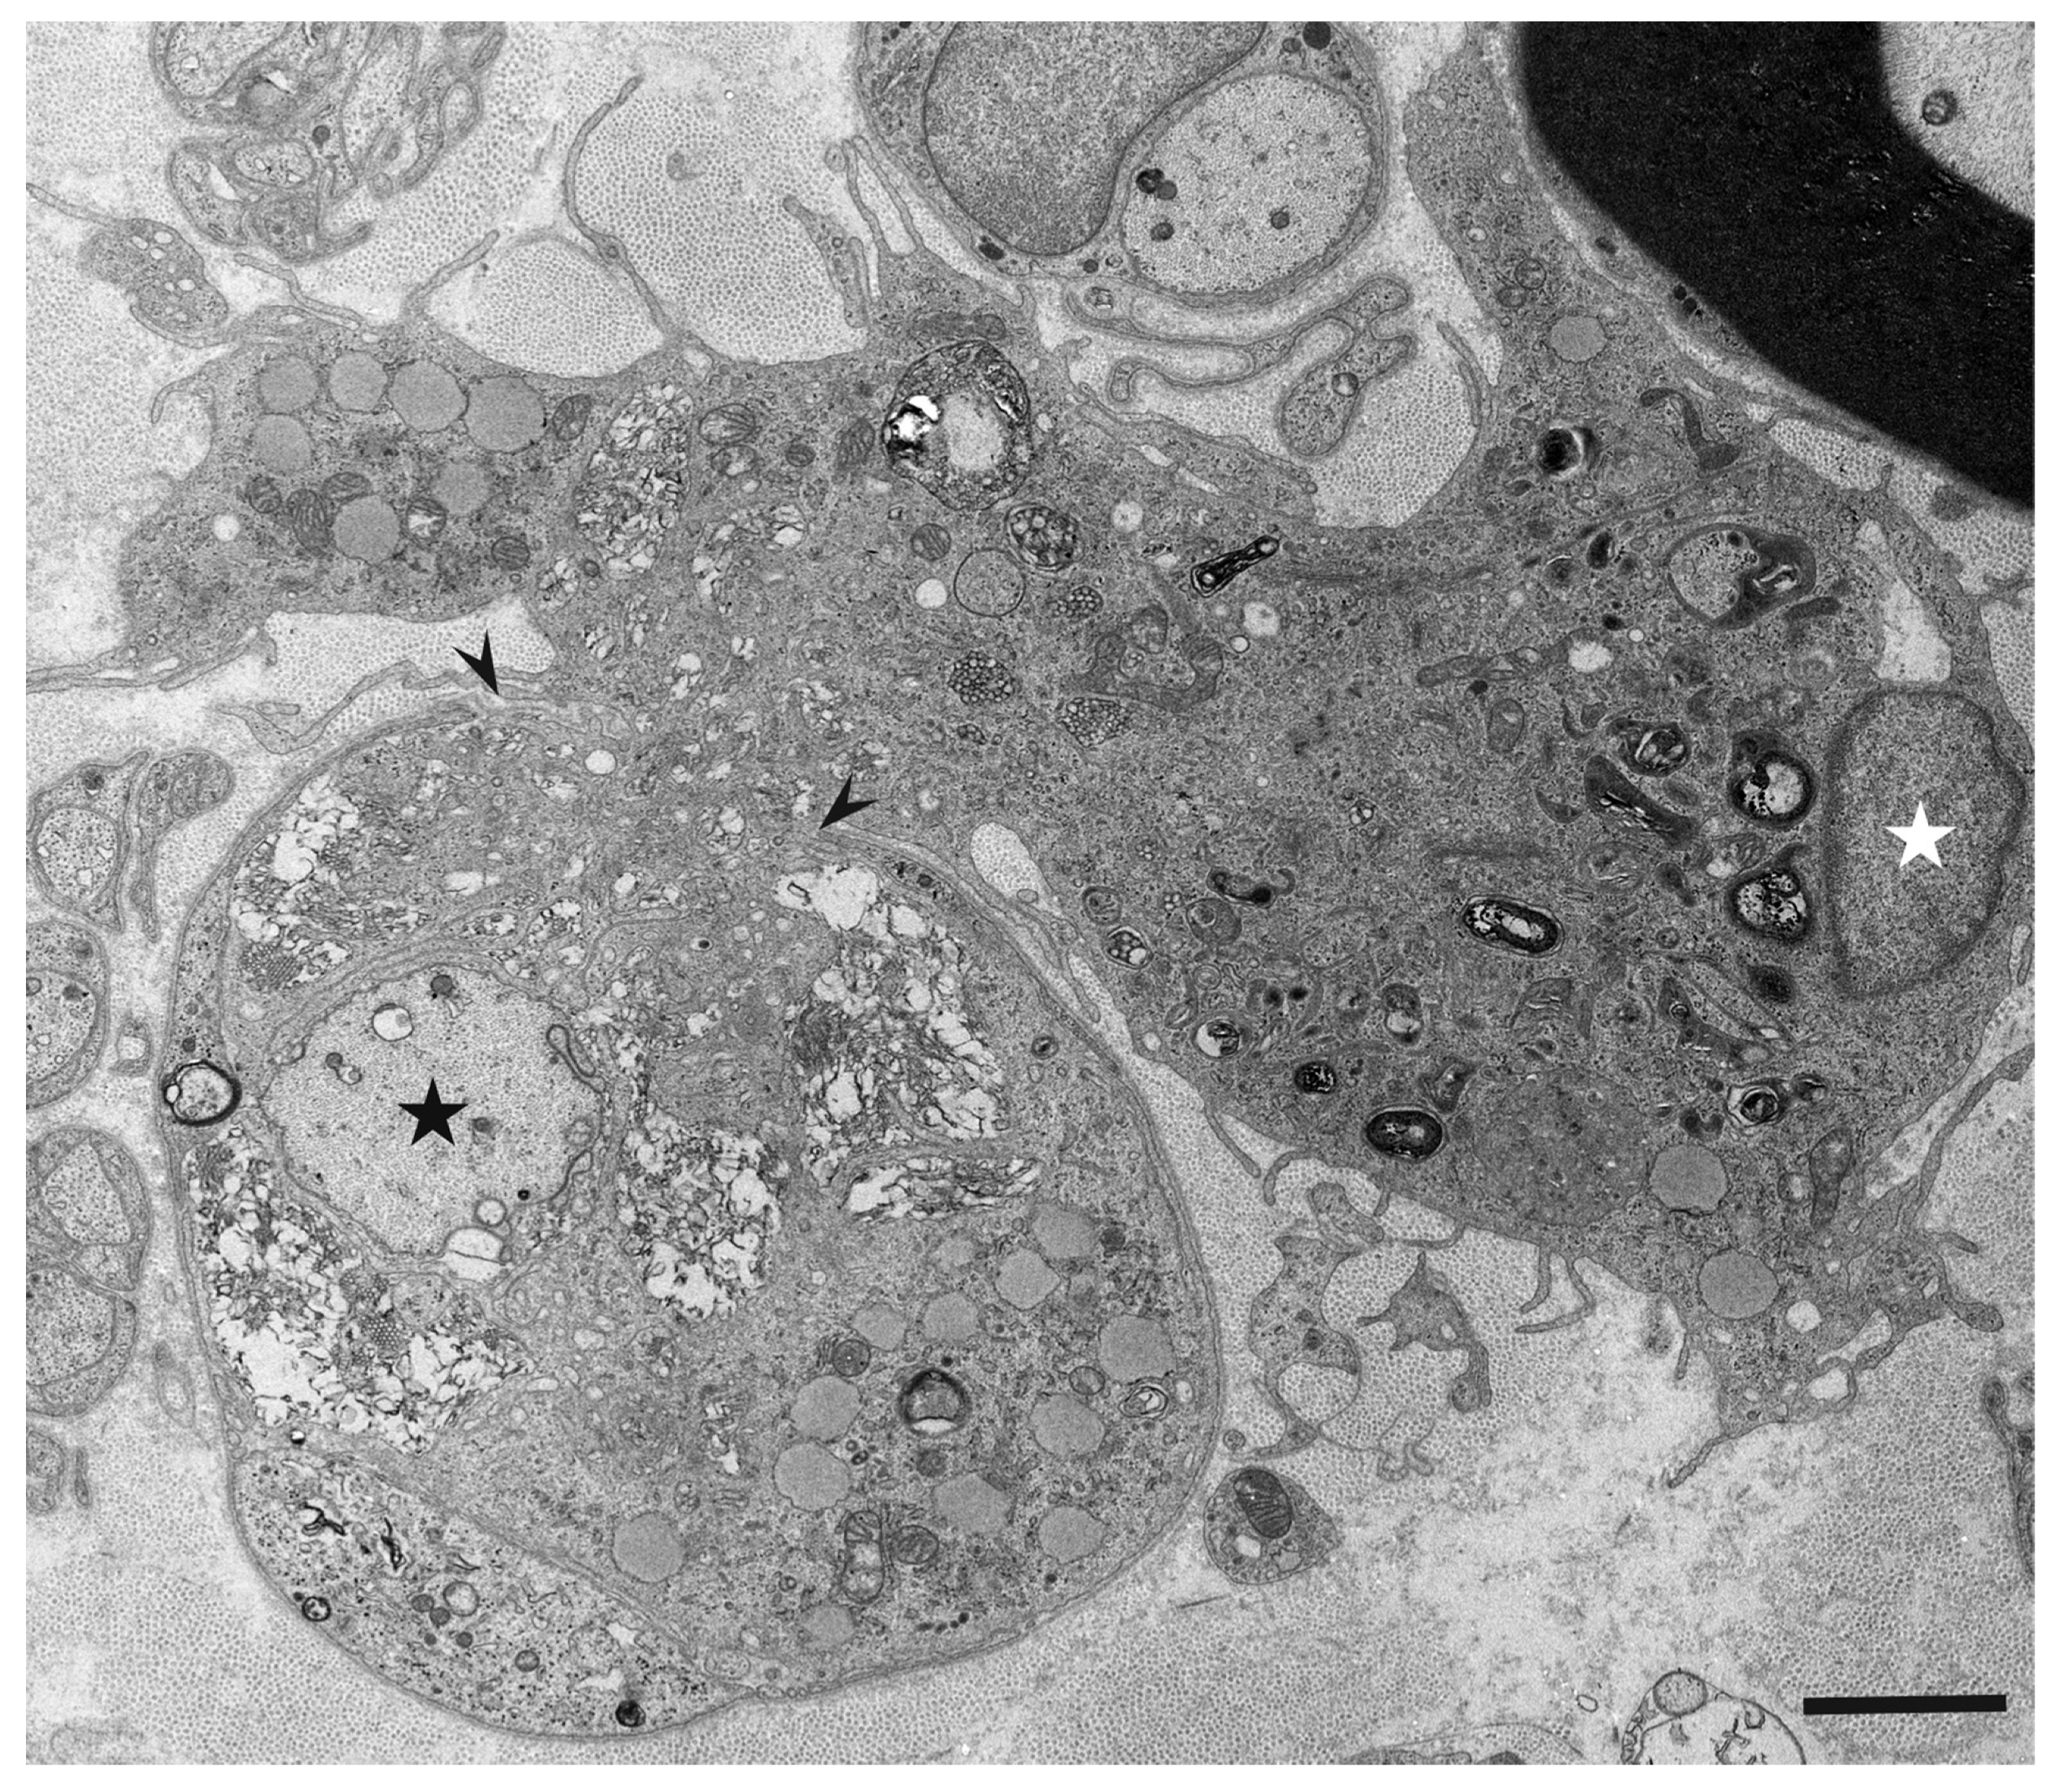

3. Morphology of Macrophages in Demyelination